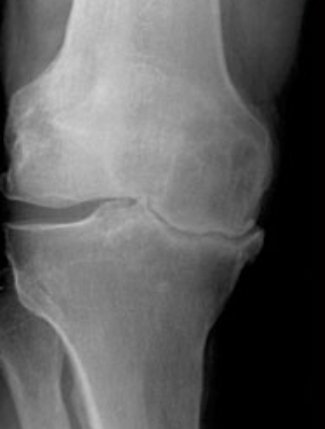

المرحلة المتوسطة: الآلام تكون متوسطة ومؤثرة على الحركة.

- ظهور انتفخات مع الألم في اوقات متفرقة.

- ظهور نتؤات عظمية في الاشعه